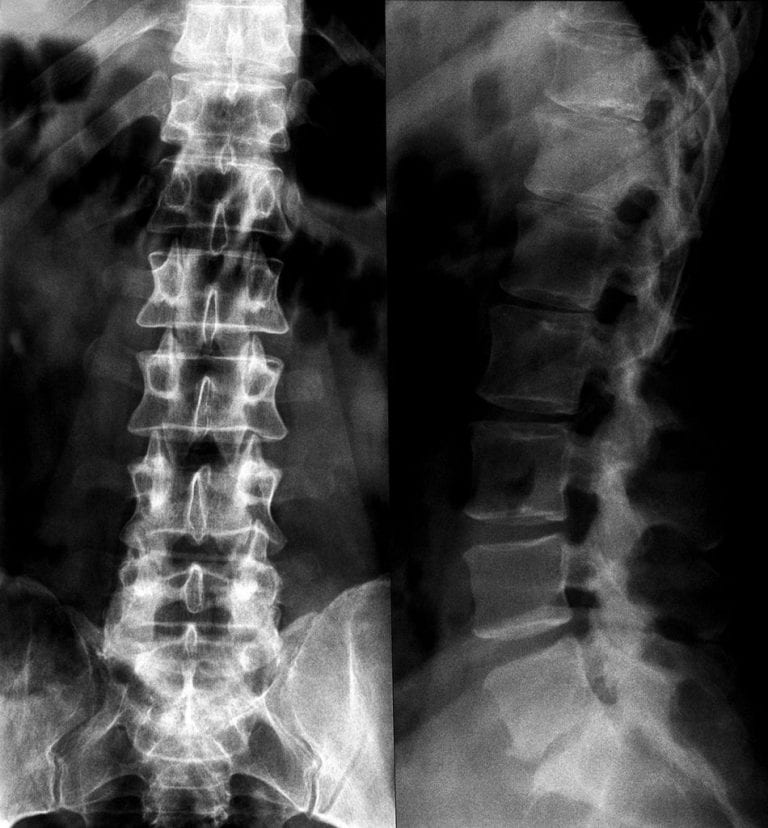

جراحة العمود الفقري بالمنظار

في عصرنا الحاضر بدأت آلام الظهر والعمود الفقري تنتشر بشكل كبير. خصوصا في حياة من يزاول مهنة الأعمال المكتبية والجلوس يوميا أمام جهاز الحاسب الآ

جراحة العمود الفقري لم تعد مُعْضلة بعد الآن

جراحة العمود الفقري لم تعد مُعْضلة بعد الآن الدكتور / بورن أنيك طاد تونج جرّاح العمود الفقري في مستشفى ويشتاني. أفصح قائلاً : إن جراحة العمود الف